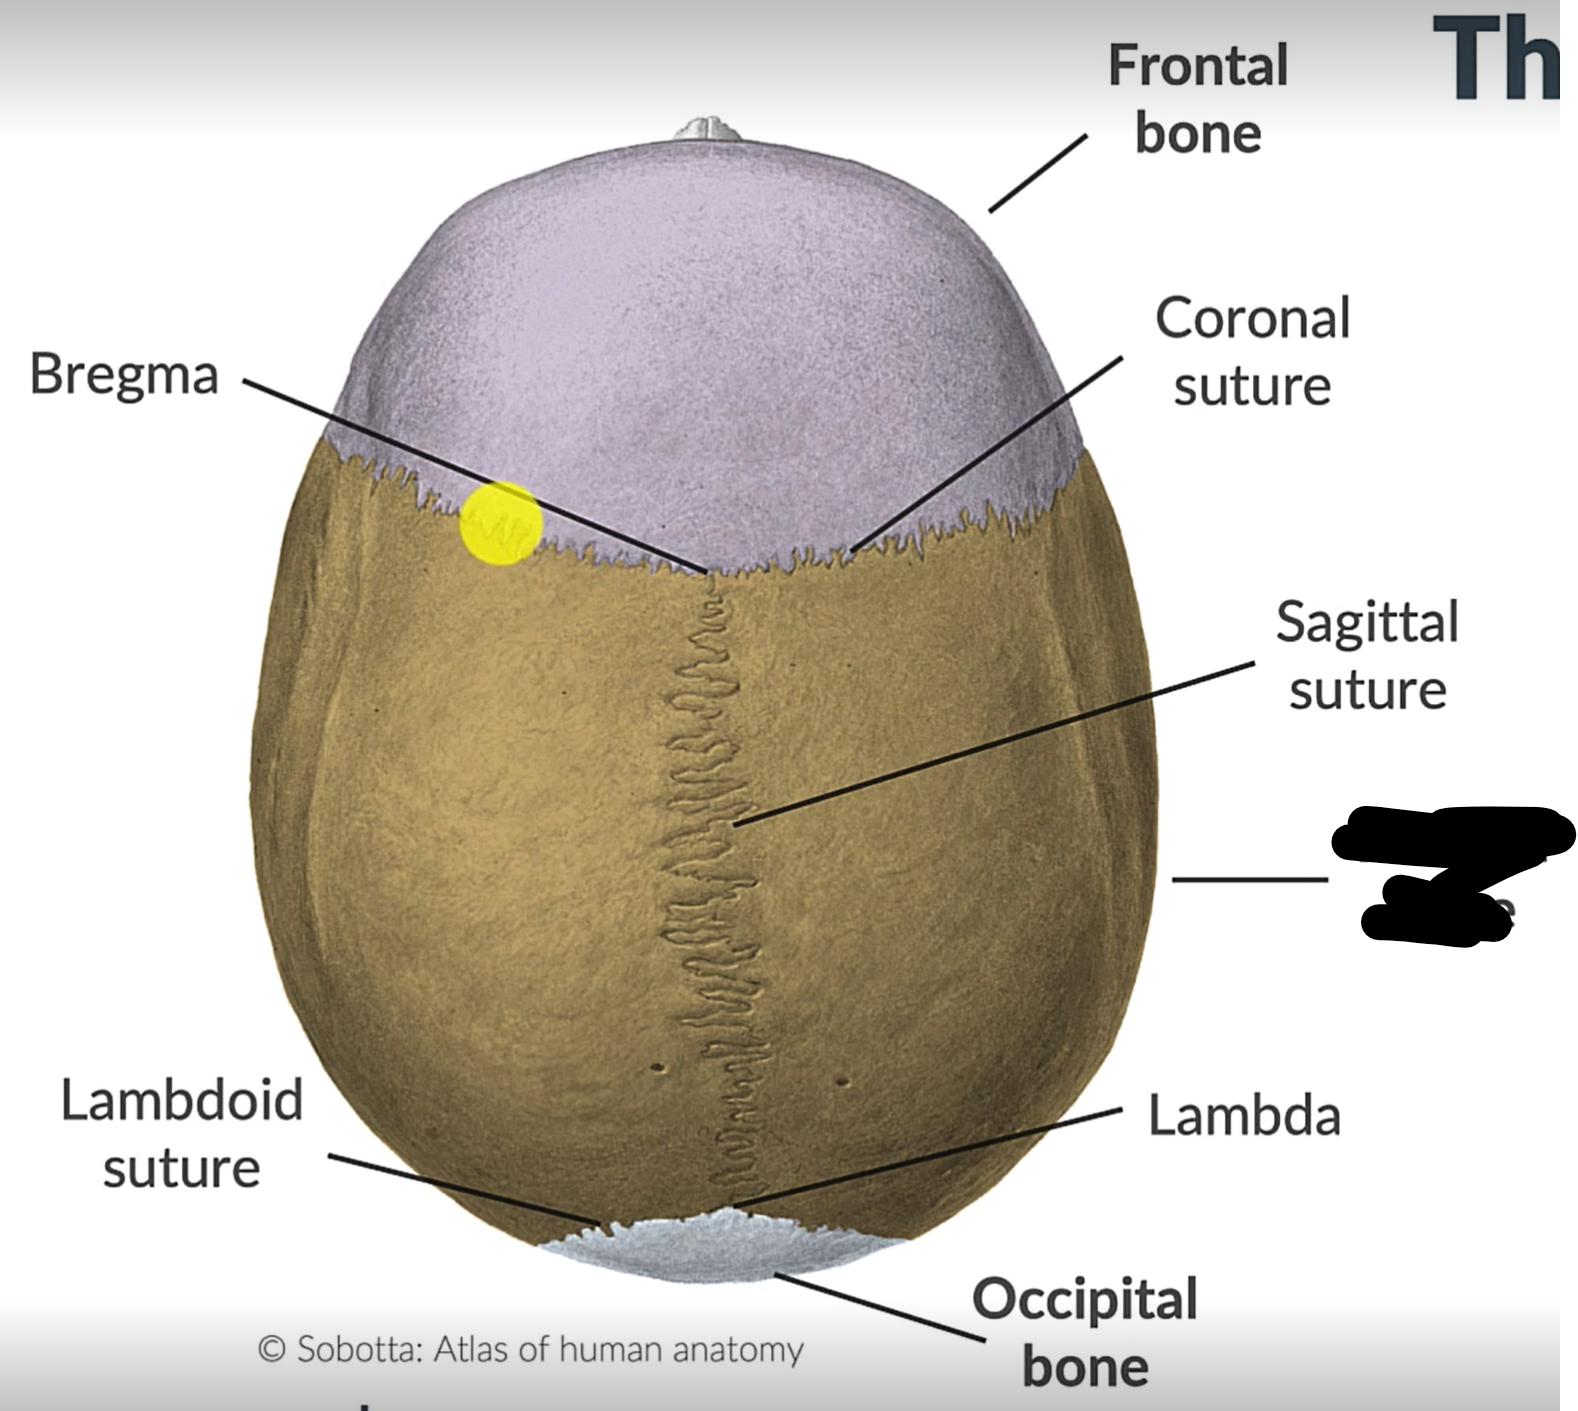

What are the 4 cranial sutures and what do they separate?

Lambdoid - separates occipital from parietal and temporal

Sagittal - extends between parietal bones

Coronal - divides frontal and parietal bones

Squamous - either side of cranium, separates temporal and parietal bones

Sagittal suture

Lambdoid suture

Occipital bone

What is the point where the frontal and parietal bones meet?

Bregma

Lambda